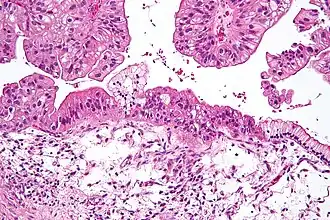

| Microfotografia de um carcinoma mucinoso do ovário, coloração H&E. | |

- Tumores mucinosos: Representam 15% dos tumores ovarianos malignos. Seu nome deriva do que produzem mucina (muco) que se espalha por toda a cavidade peritoneal. Eles aparecem em mulheres mais jovens, geralmente diagnosticada em estágios iniciais e têm um prognóstico melhor do que serosa. Bom prognóstico com 77% de sobrevivência em 5 anos.